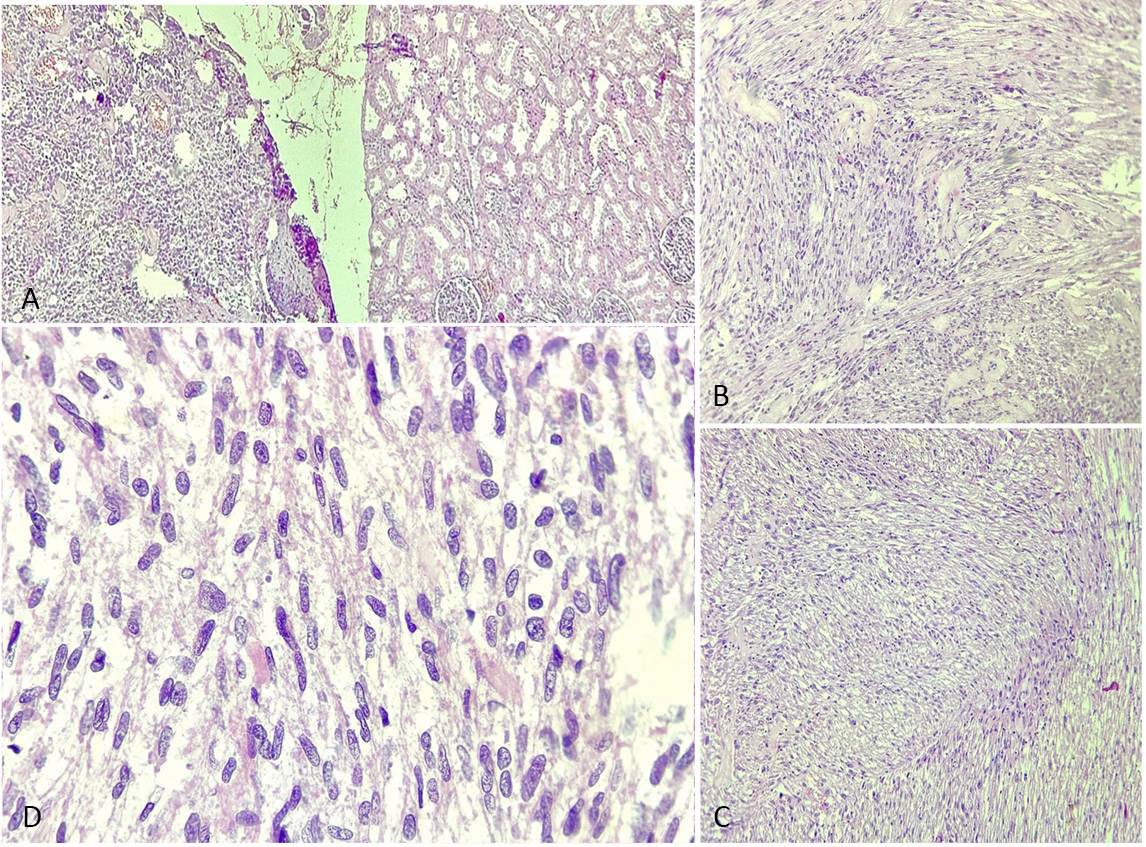

On gross examination, the right kidney measured 11x10x5 cm and weighed approximately 500gm. A mass was identified involving the upper and middle pole of the kidney and measuring 7x6x5cm. Capsular breach was identified, and the mass was seen extending to perinephric fat. The mass macroscopically seemed to arise from renal pelvis. Hilar structures could not be identified. On serial sectioning, corticomedullary junction was identified. Tumor on serial sectioning appeared solid white in appearance with hemorrhagic areas. On microscopic examination, the tumor was composed of plump spindle cells arranged in bundles and long intersecting fascicles, with individual cells having oval to elongated, blunt-ended nuclei and moderate to abundant pale to eosinophilic cytoplasm, showing moderate to marked nuclear pleomorphism. Mitotic figures including atypical ones were numerous (Figure 3). Tumor necrosis was seen involving <50% of the total tumor area. Lymphatic or vascular invasion were not identified. Margins of resection were free of tumor. On immunohistochemistry, the tumor cells were positive for vimentin, desmin and smooth muscle actin and negative for CK7, PanCK, MyoD1, S100, p53, CD10, HMB-45 and EMA (Figure 4). Histopathological reporting was done according to CAP cancer templates [7]. Based on the morphological and immunohistochemical profile, a diagnosis of Well-differentiated leiomyosarcoma was made. The tumor was involving the upper and middle pole of right total nephrectomy specimen and was involving the perinephric fat and reaching upto the gerota’s fascia. The pelvic calyceal system was seen involved by the tumor, however renal sinus was free of tumor. Final diagnosis was given as Leiomyosarcoma, FNCLCC grade 1, of right kidney with pTNM staging as pT3aNxMx. No regional lymph nodes were submitted.